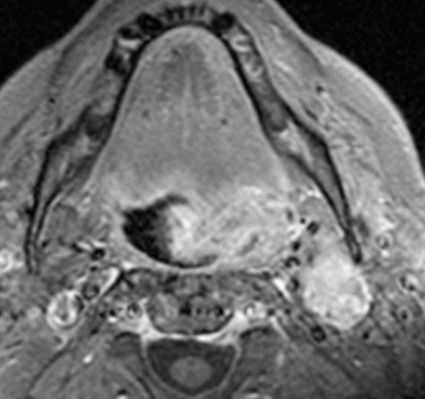

МРТ при плоскоклеточном раке ротоглотки

Плоский эпителий выстилает слизистую ротоглотки, гортаноглотки, и полости рта. Плоскоклеточный рак языка, миндалин, гортаноглотки, и и полости рта, включая губы, очень распространен. В ротоглотке, наиболее частой локализацией плоскоклеточного рака служит передняя миндалина. Плоскоклеточный рак с этого места может глубоко распространяться под невовлеченной слизистой оболочкой. Типично распространение через межмышечные щели в окологлоточное пространство и сонное пространство. Часто поражаются цепочки лимфатических узлов вдоль внутренней яремной вены. При клиническом обследовании очень трудно правильно оценить поражение слизистых оболочек и распространение рака.

Постановка ротоглоточного плоскоклеточного рака основывается на размерах опухоли и инвазии в соседние структуры. Поэтому при МРТ мягких тканей этой области нужно обратить особое внимание на переход опухоли в глубокие пространства, особенно в окологлоточное, сонное, и превертебральное. При МРТ сонных пространств также важно оценить лимфаденит.

МРТ мягких тканей шеи с контрастированием. Распространения рака ротоглотки на парафарингеальное пространство.

Плоскоклеточный рак основания языка также может прорасти в соседние глубокие пространства. Встречается периневральное распространение. Кроме того, следует определить линии пересечения опухоли, как это имеет значения для выбор объема операции. Плоскоклеточный рак основания языка имеет склонность вторгаться книзу в подчелюстное пространство и спускаться вплоть до надгортанника. Кроме того, при МРТ мягких тканей следует оценить инвазию нижней челюсти.

Что касается глубинных структур, особое внимание при МРТ мягких тканей шеи следует уделить распространению опухоли на превертебральное пространство. Инвазия глубокой фасции шеи, длинных мышц шеи, или самого позвоночника, определяемые при МРТ мягких тканей шеи, ставят вопрос об обширной операции. Кроме того, поражение сонной артерии ставит вопрос о резектабельности. Некоторые хирурги считают, что если опухоль по данным МРТ мягких тканей шеи охватывает меньше 50% сонной артерии она может быть от нее отделена. Вероятность невозможности удаления опухоли заметно увеличивается, когда по данным МРТ мягких тканей шеи она окружает более 75% сонной артерии. Вовлечение в процесс жевательного пространства может происходить с ротоглотки. Вовлечение жевательного пространства должно насторожить в плане прорастания основания черепа, особенно, через овальное окно и/или вдоль крылонебной ямки. Другие пути распространения через основание черепа идут вдоль сонного канала, через яремное отверстие, и евстахиеву трубку